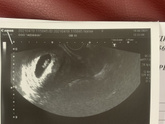

Девочки, пришла коагулограмма, вроде как показатели протромбин по квику и протромбиновое время пришли в норму, я так понимаю это на фоне приёма препаратов сначала пила курантил 75, два дня назад перешла на тромбо асс, через сколько ее нужно снова пересдать … Читать далее